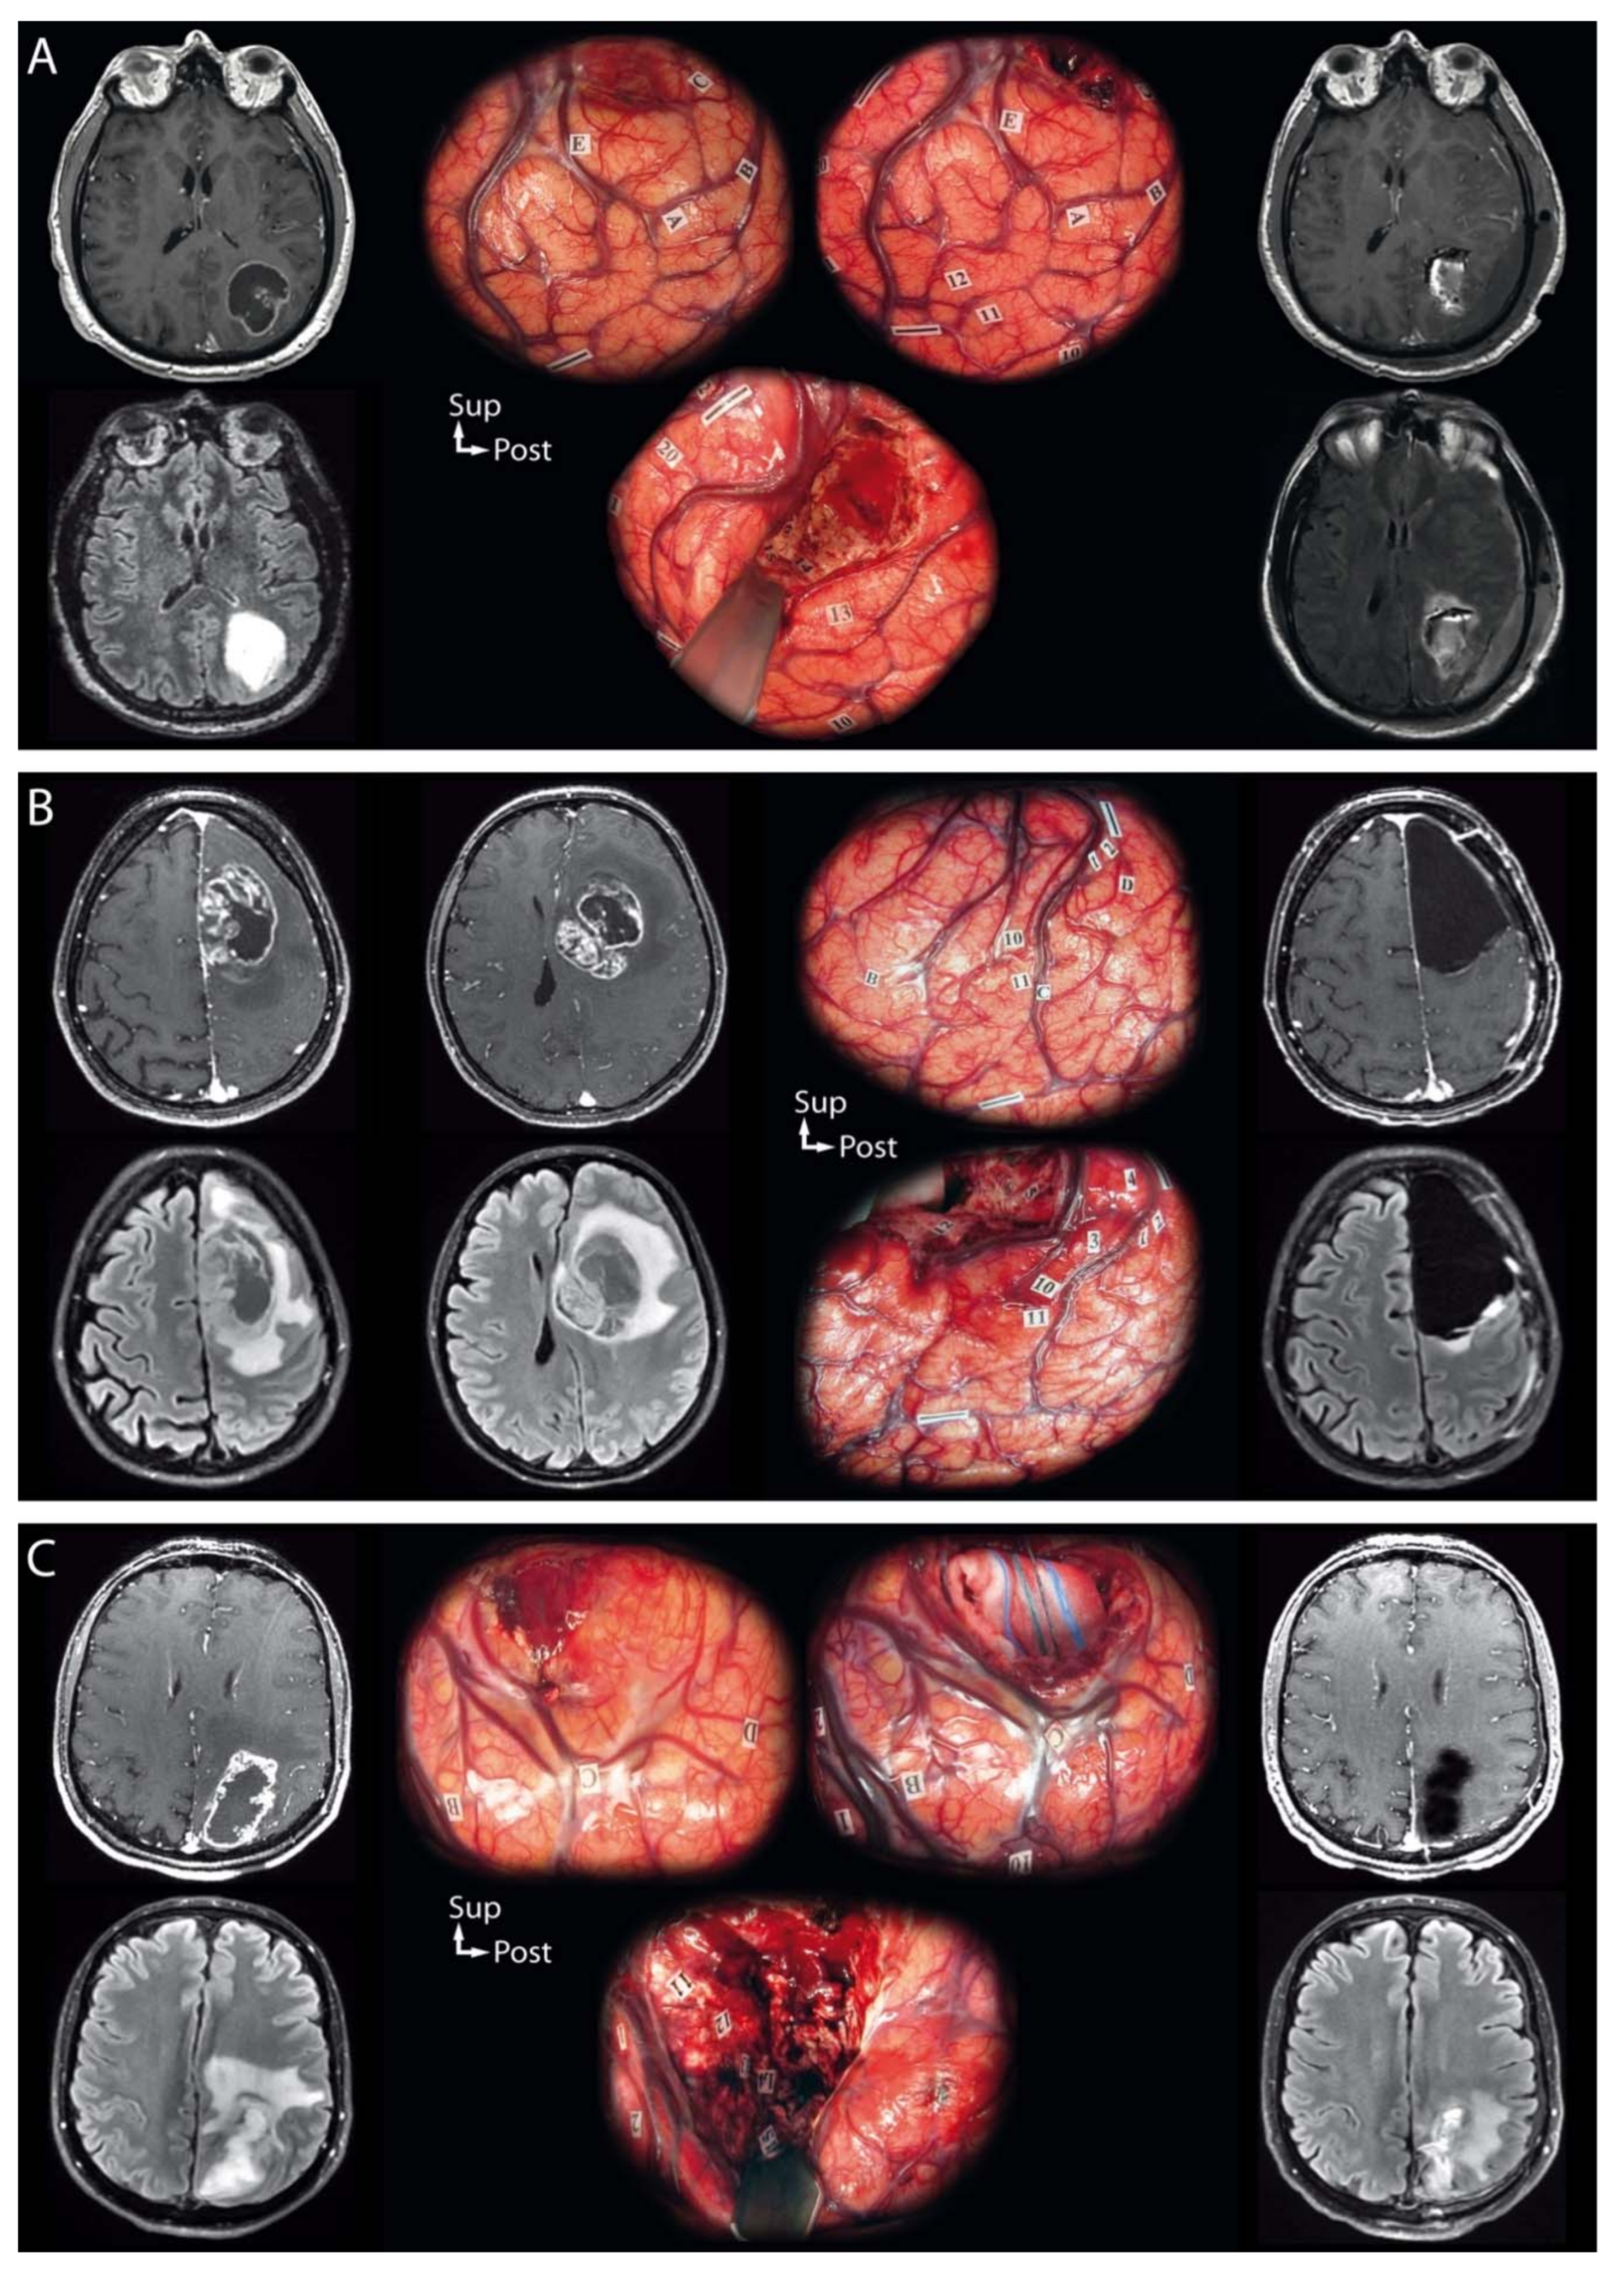

3.2. Awake Surgery Procedure

- Pallud, J.; Rigaux-Viode, O.; Corns, R.; Muto, J.; Lopez, C.L.; Mellerio, C.; Sauvageon, X.; Dezamis, E. Direct electrical bipolar electrostimulation for functional cortical and subcortical cerebral mapping in awake craniotomy. Practical considerations. Neurochirurgie 2017, 63, 164–174. [Google Scholar] [CrossRef] [PubMed]

- Pallud, J.; Mandonnet, E.; Corns, R.; Dezamis, E.; Parraga, E.; Zanello, M.; Spena, G. Technical principles of direct bipolar electrostimulation for cortical and subcortical mapping in awake craniotomy. Neurochirurgie 2017, 63, 158–163. [Google Scholar] [CrossRef] [PubMed]